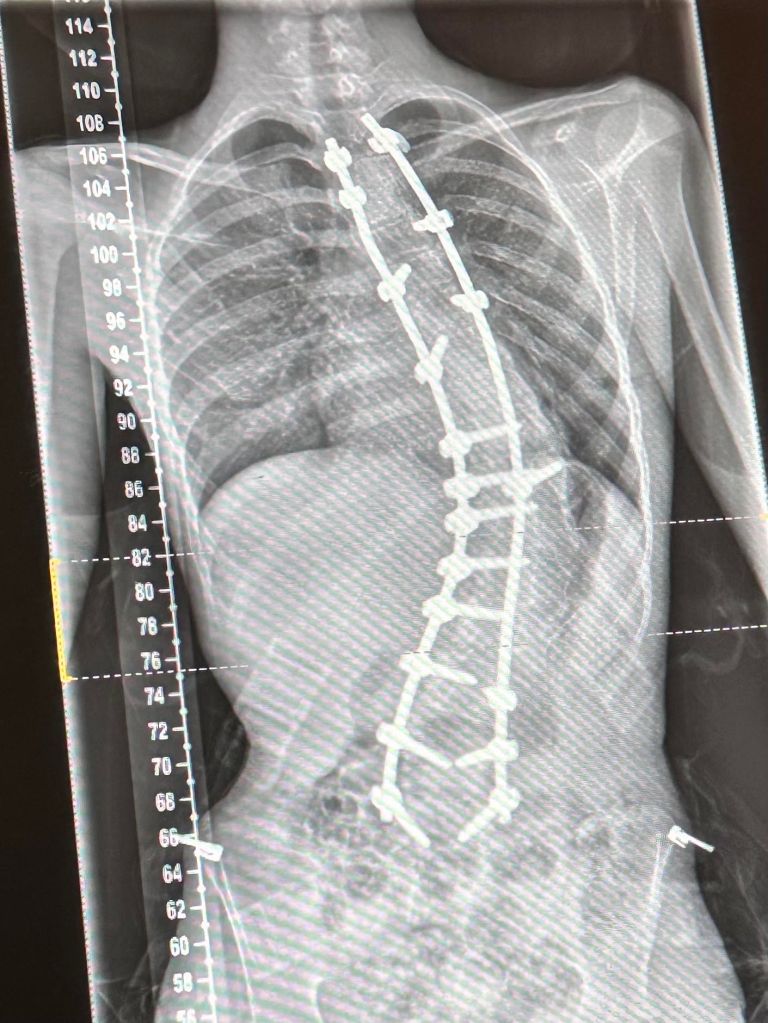

We’ve been back to Sheffield and Mr Brakewell was very pleased with his recovery, and the fact that he’s managing without pain relief. Well done T! You can see below his comparative before and after x-rays, and also the large amount of titanium in his back!